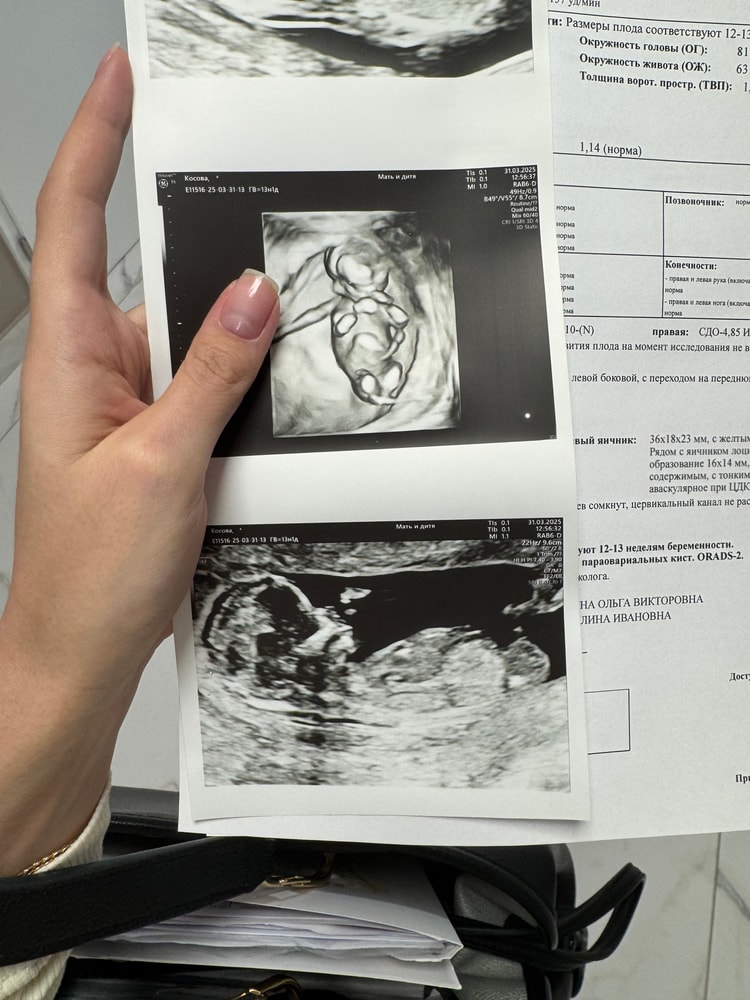

1 скрининг

Скрининг.. у нас был в 13.1 недель. Такое классное часовое УЗИ со всеми подробностями! Невероятные эмоции от осознания, что вот он человек. А еще несколько месяцев назад это казалось несбыточной мечтой

Прикрепила фото. Ну и классическое, на кого похож ? ☺️🩷🩵